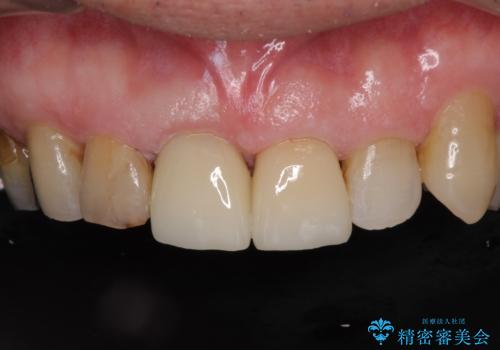

差し歯(被せ物)のやりかえ 上の前歯で印象が明るく

- 前歯がぐらつくことを主訴にご来院された患者様です。ご本人は抜歯と考えており、インプラント以外の治療をご希望でした。しかしながらぐらついていた原因は、古い差し歯が取れかけていたことでした。

遠方から通院されること、仕事上短期間で治療したいとのことを考慮して、残っている歯はかなり小さいものの、保存すべきと判断して当日処置から行いました。

西日本から新幹線でご来院された患者様です。前歯は都内の医院でやりたいとのことで、はるばる通院してくださいました。通院回数が最小限になるよう工夫しました(1回あたりの時間は長くなります)。

残っている歯が小さいと、差し歯はぐらつきやすくなりますが、その形態によっては抜歯を回避できることがあります。